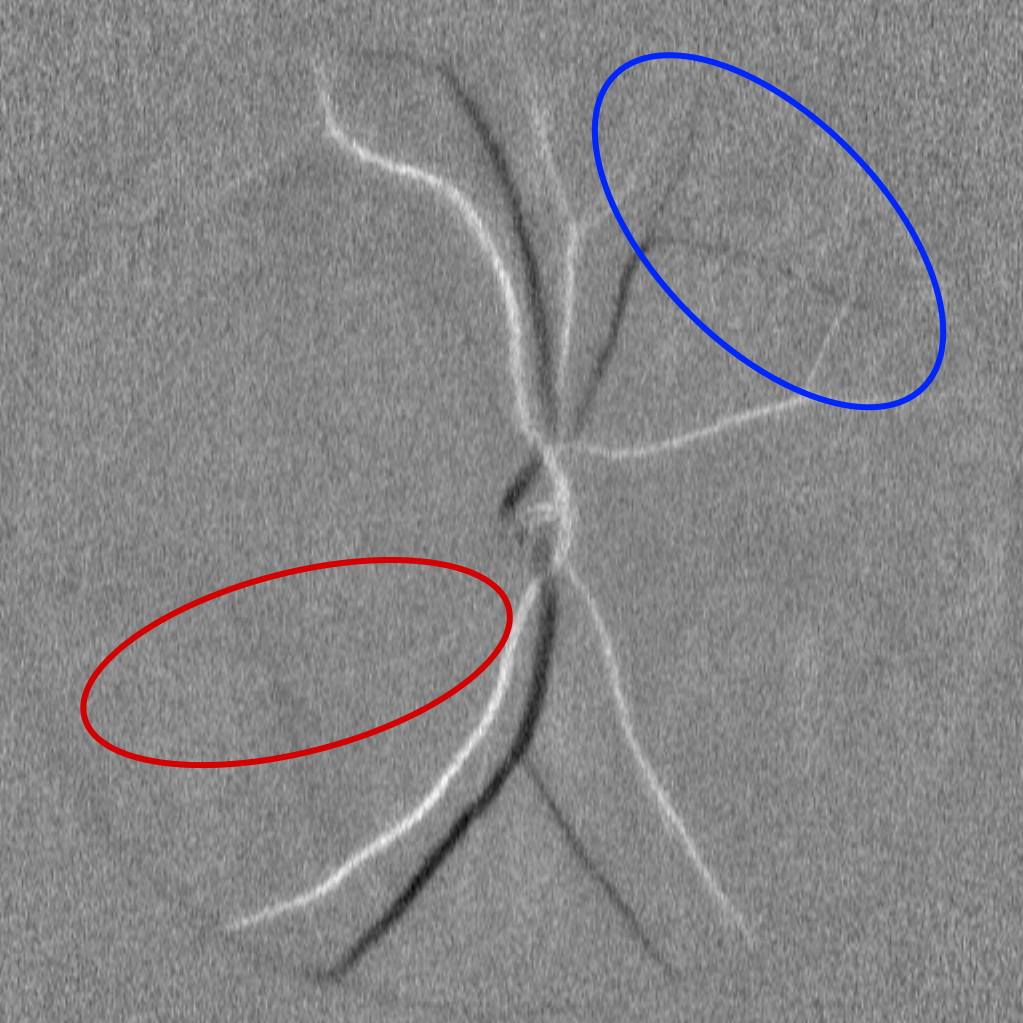

(c) M0 + diasys + corr.

Fig. 3: Segmentation results of WNet (top) and U-Net (bottom) trained with different inputs. With only M0, the U-Net shows more misclassifications than WNet (b). Both improve greatly when using the diasys and correlation maps, yielding nearly identical outputs (c).

The most straightforward approach consists in directly performing semantic segmentation on M0 images. The results of this strategy are reported in Table 1. Overall, all models achieve limited performance, with WNet obtaining the best results. Most architectures successfully delineate the retinal vasculature but fail to accurately distinguish between arteries and veins (Fig 3b), resulting in better segmented arteries, likely due to the higher signal-to-noise ratio and more pronounced pulsatile Doppler signature of arterial flow (Table 2). Other models such as SwinUnet even struggle to segment vessels precisely. Only WNet manages to perform a consistent classification of arteries and veins (Fig 3b); this can be attributed to its hybrid design, where convolutional layers ensure accurate spatial segmentation, while transformer layers capture the global context useful for classification. In general, the best-performing models rely on hybrid transformer–convolution designs (WNet, CSTA-Net) or feature enhancement (MSUNet, UNet++, CE-Net). However, the basic UNet still outperforms several of these more complex models and remains a strong baseline.

The results are summarized in Table 1. The proposed strategy substantially improves performance across all models, reduces variability, particularly for vein segmentation, and eliminate the performance gap observed between arteries and veins when using M0 alone (Table  2). Previously, only the WNet achieved a Dice score above 0.7, exceeding the second-best model by more than 0.05 and the standard UNet by about 0.15. With the proposed approach, almost all models now reach Dice scores above 0.8, within 0.03 of each other, with similar trends across other metrics. This indicates that architectures originally designed for spatial feature extraction can effectively exploit temporal information encoded in the correlation and diasys maps (Fig. 3).